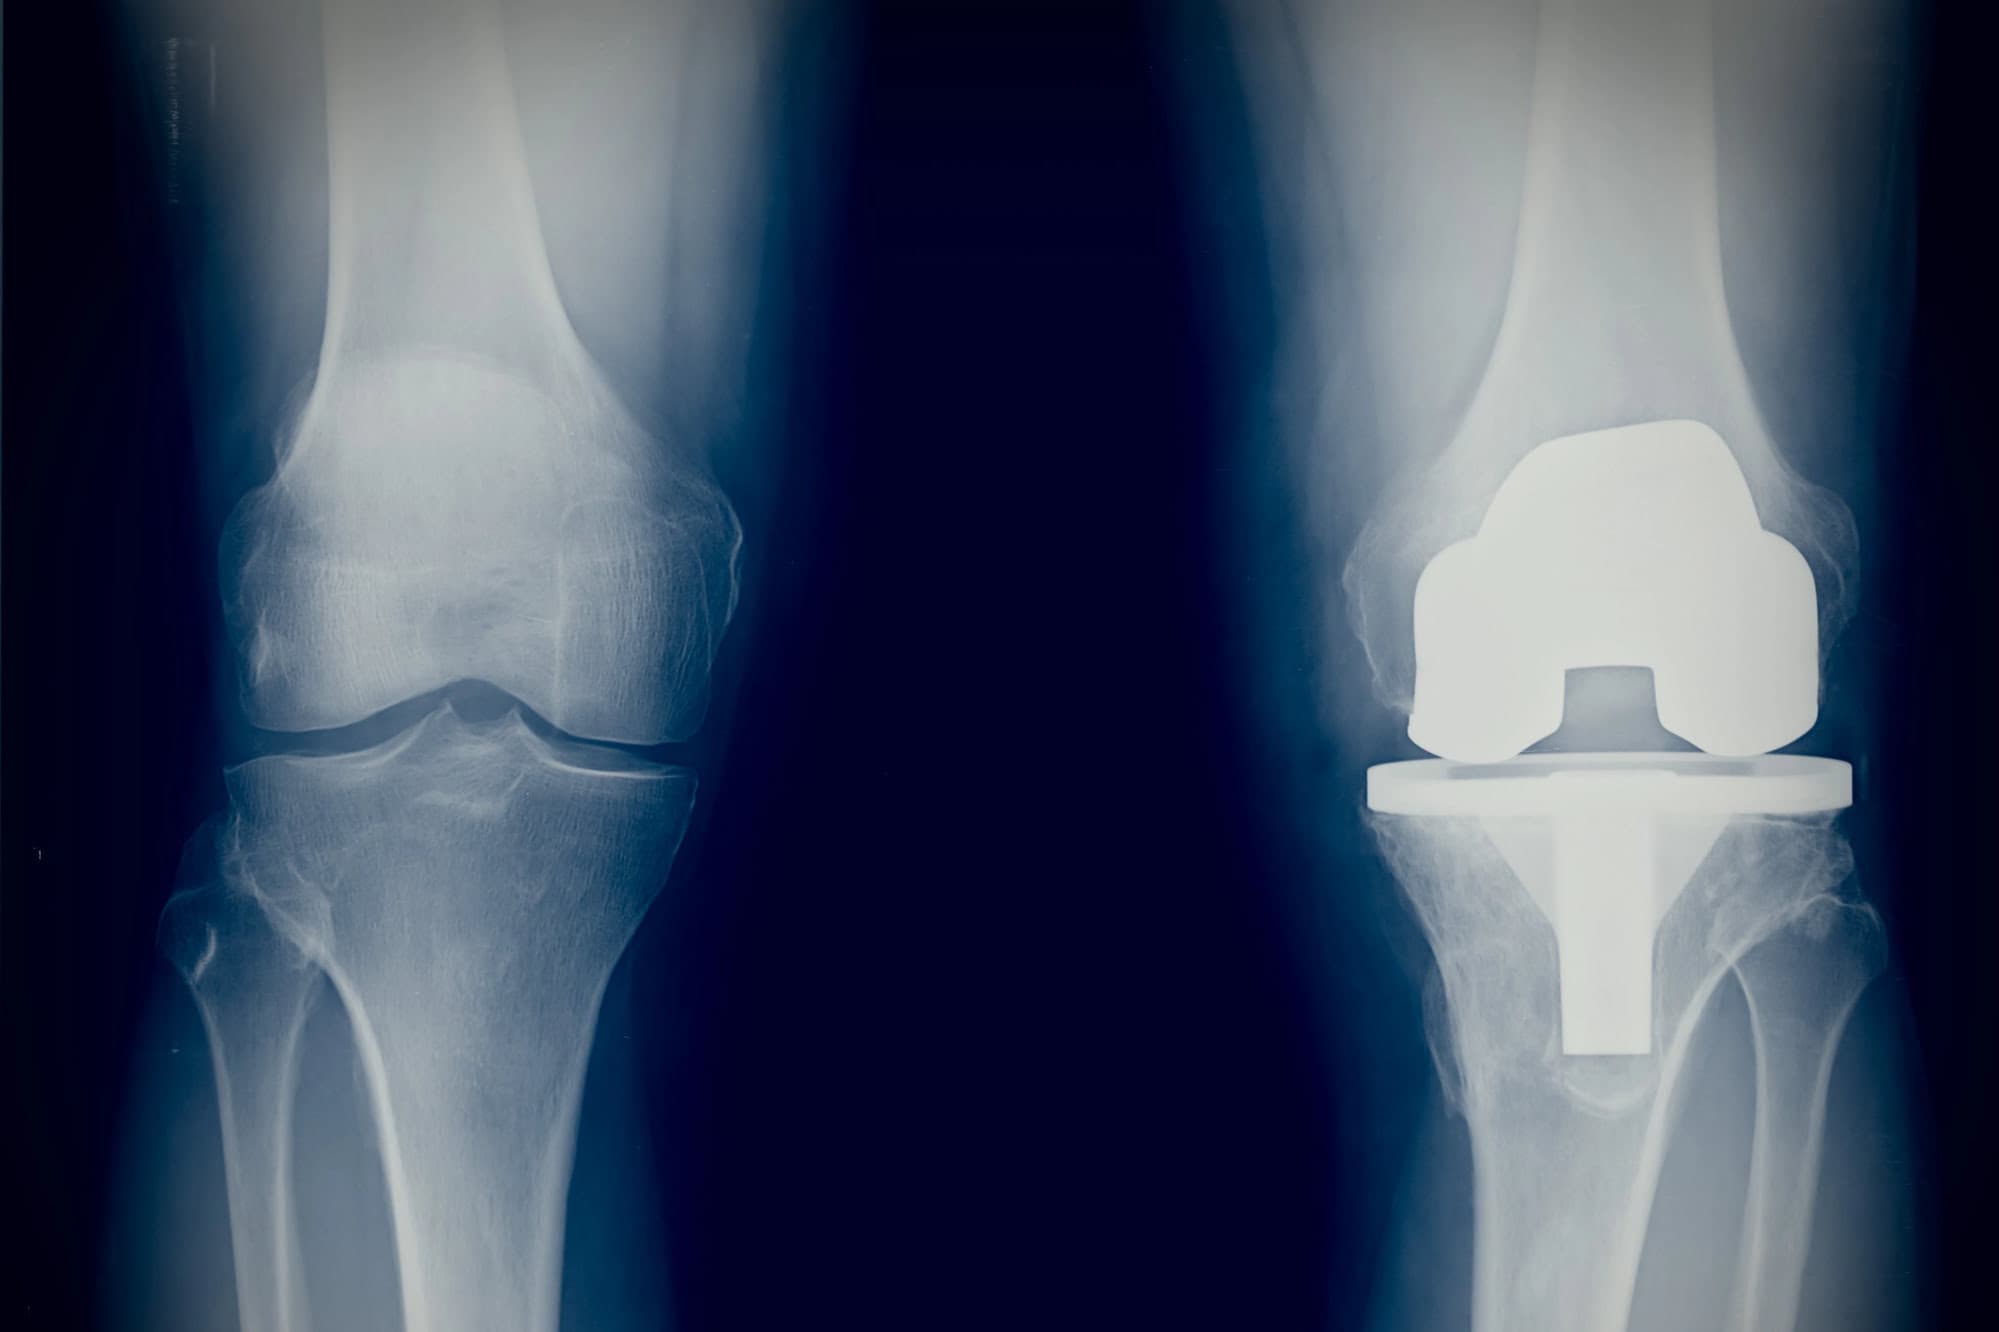

Knieprothese-OP

Für Patienten mit fortgeschrittener Kniearthrose kann ein künstliches Kniegelenk die Schmerzen deutlich reduzieren und die Mobilität langfristig verbessern. Wir bieten:

- Individuelle OP-Planung und Auswahl moderner Implantate

- Teil- oder vollzementierte Prothesen je nach Befund

- Minimal-invasive Zugänge (wenn möglich)

- Schonende OP-Techniken mit Fokus auf schneller Mobilisation

- Strukturierte Nachbehandlung für eine sichere Rückkehr in den Alltag